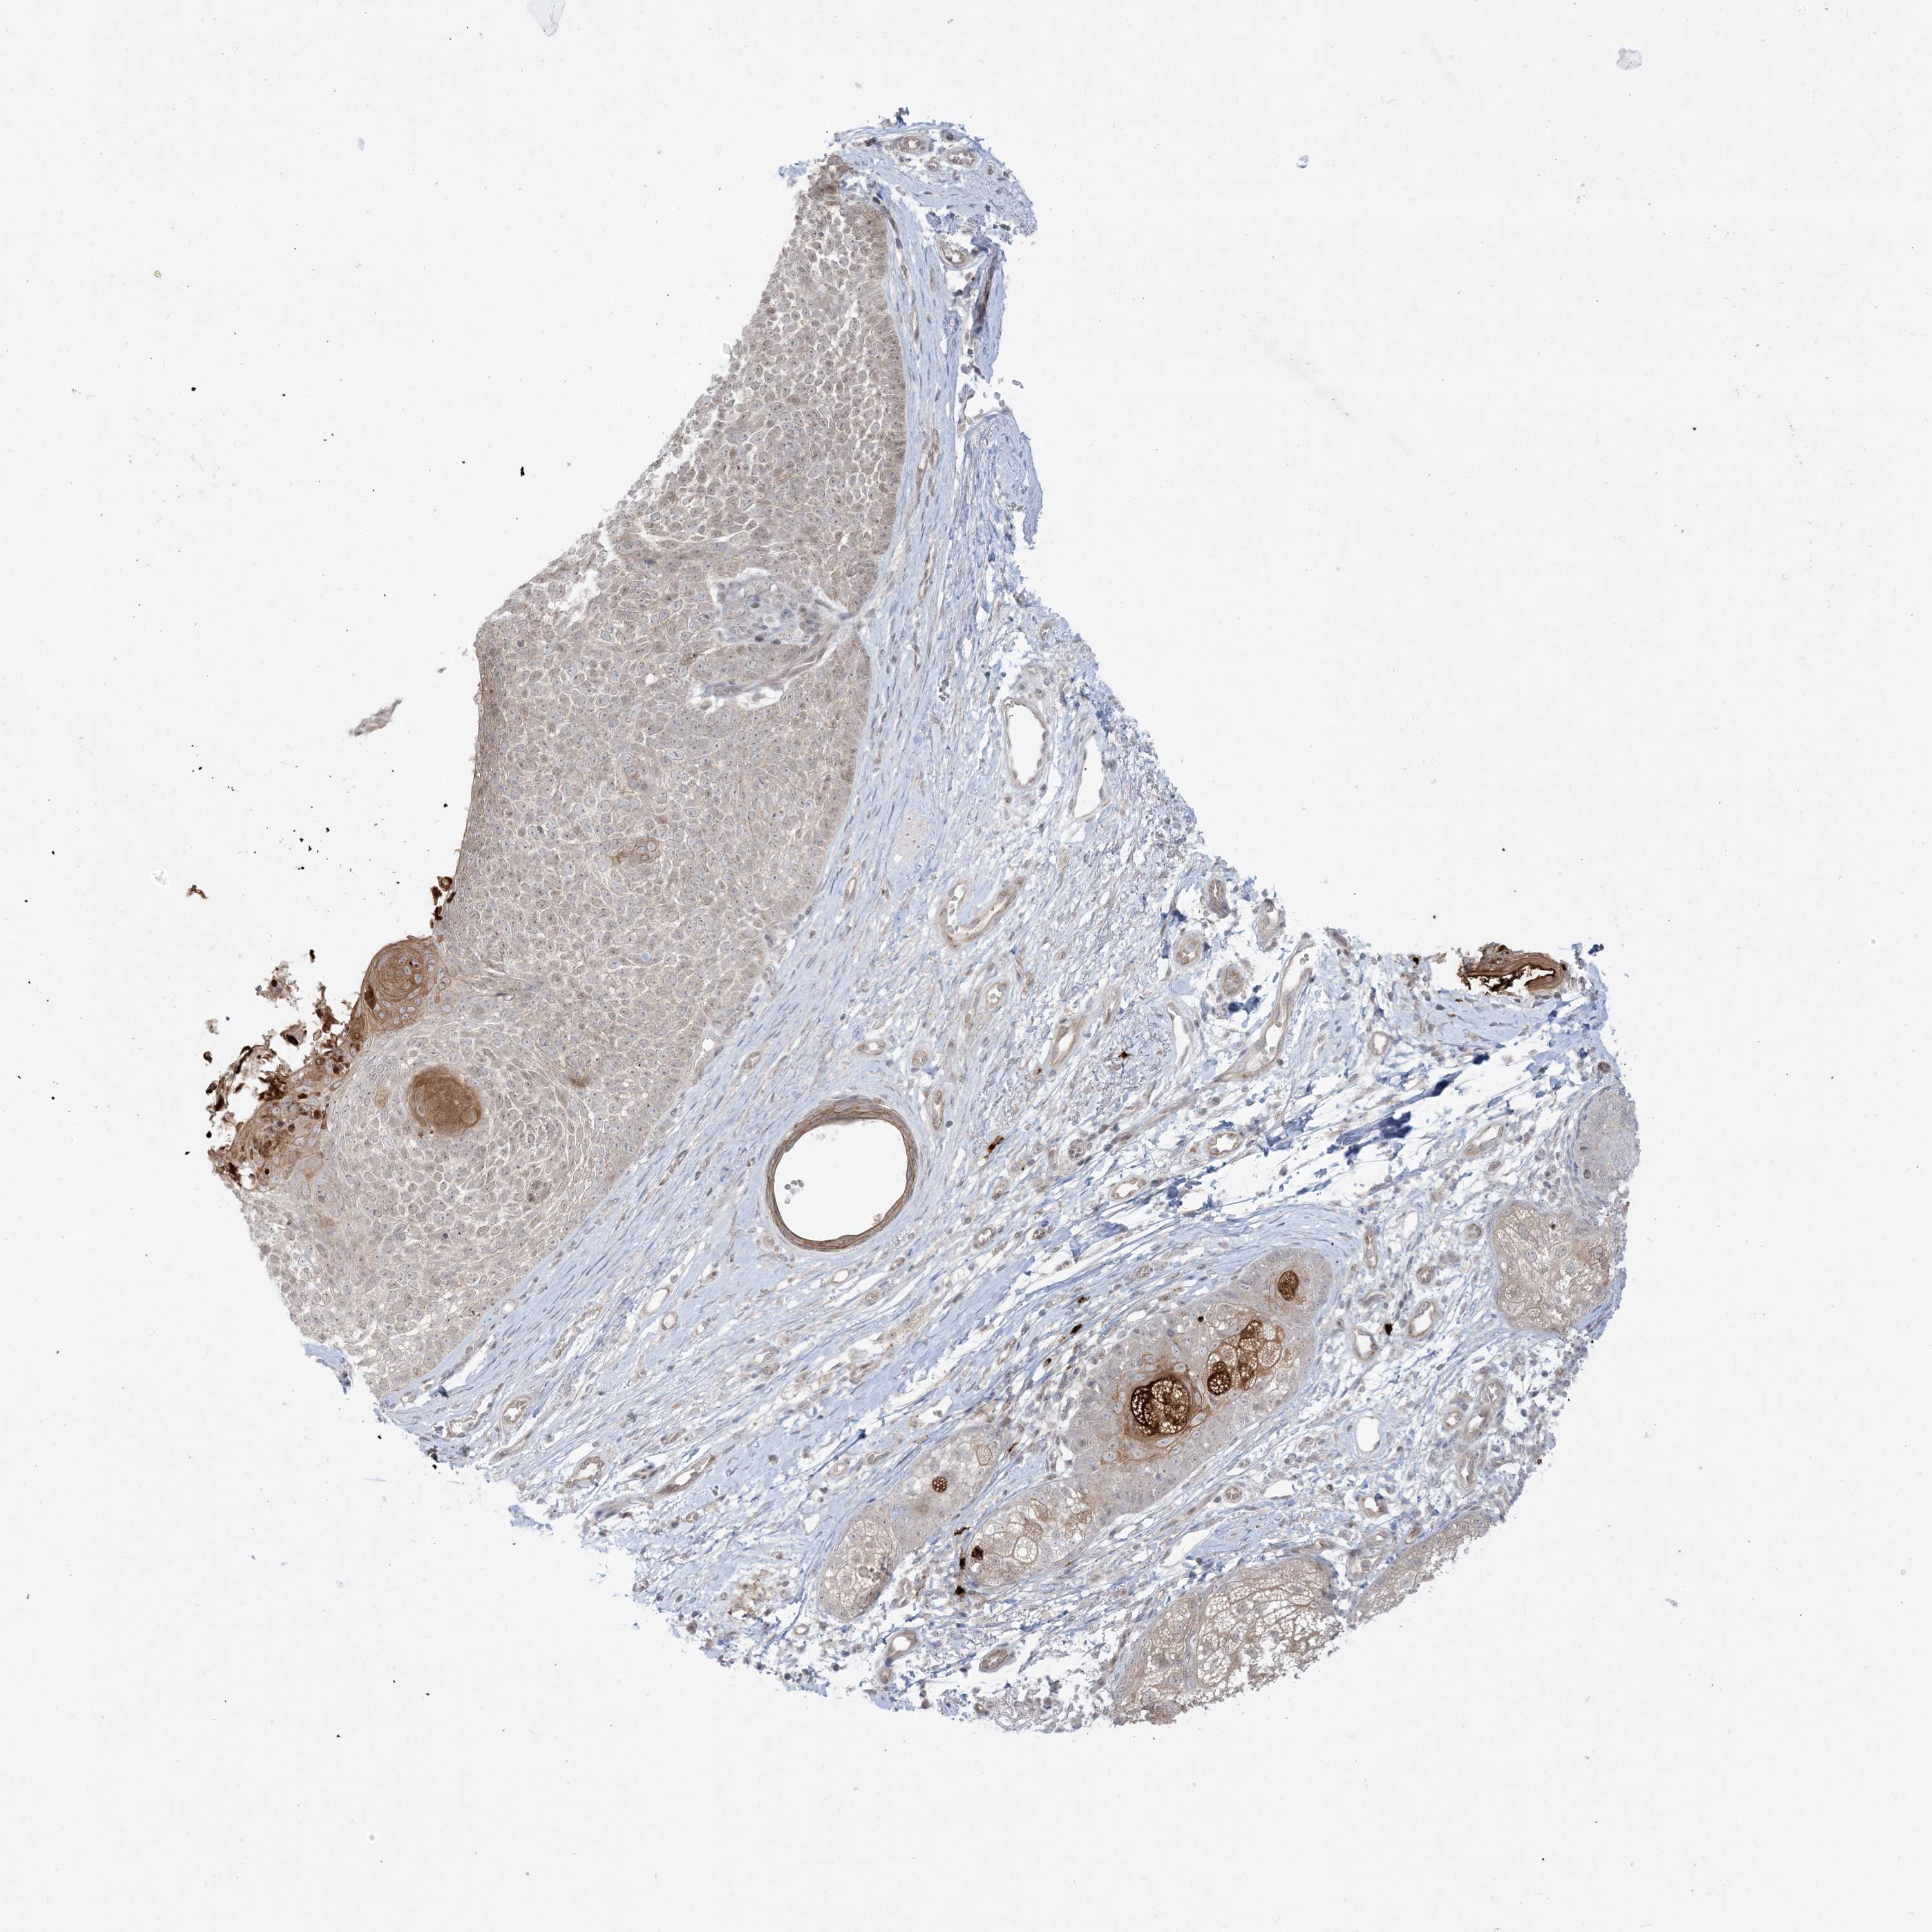

SKIN CANCER - Protein expressioni

A mouse-over function shows sample information and annotation data. Click on an image to view it in a full screen mode. Samples can be filtered based on level of antibody staining by selecting one or several of the following categories: high, medium, low and not detected. The assay and annotation is described here.

Each image is clickable and will lead to virtual microscopy that enables deeper exploration of all samples and also displays staining intensity scores, fraction scores and subcellular localization as well as patient and tissue information for each sample.

Antibody CAB032952

Squamous cell carcinoma, metastatic, NOS